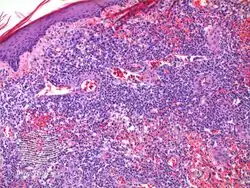

It can appear very similar to anaplastic large cell lymphoma.[4] Type "A" is CD30 positive, while type "B" is CD30 negative.[5]

It has been described as "clinically benign but histologically malignant."[6]